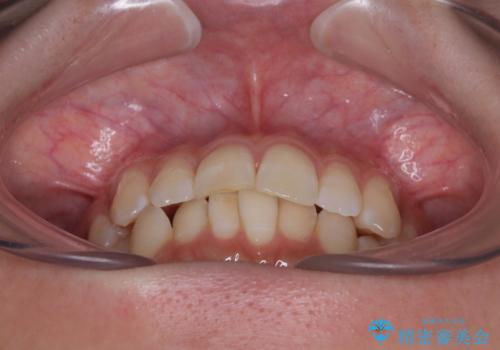

- 上下前歯の重なりを気にして来院された患者様です。

安価なインビザラインパッケージを用いての治療を希望されており、デコボコの程度が中等度であったため、インビザライン・モデレートを用いて矯正治療を行うこととしました。

インビザライン・モデレートは、製作できるアライナーの枚数に制限があるため、移動可能な量に限りがあるものの、インビザライン・ライトよりも枚数が多いため、幅広い症例に対応可能です。